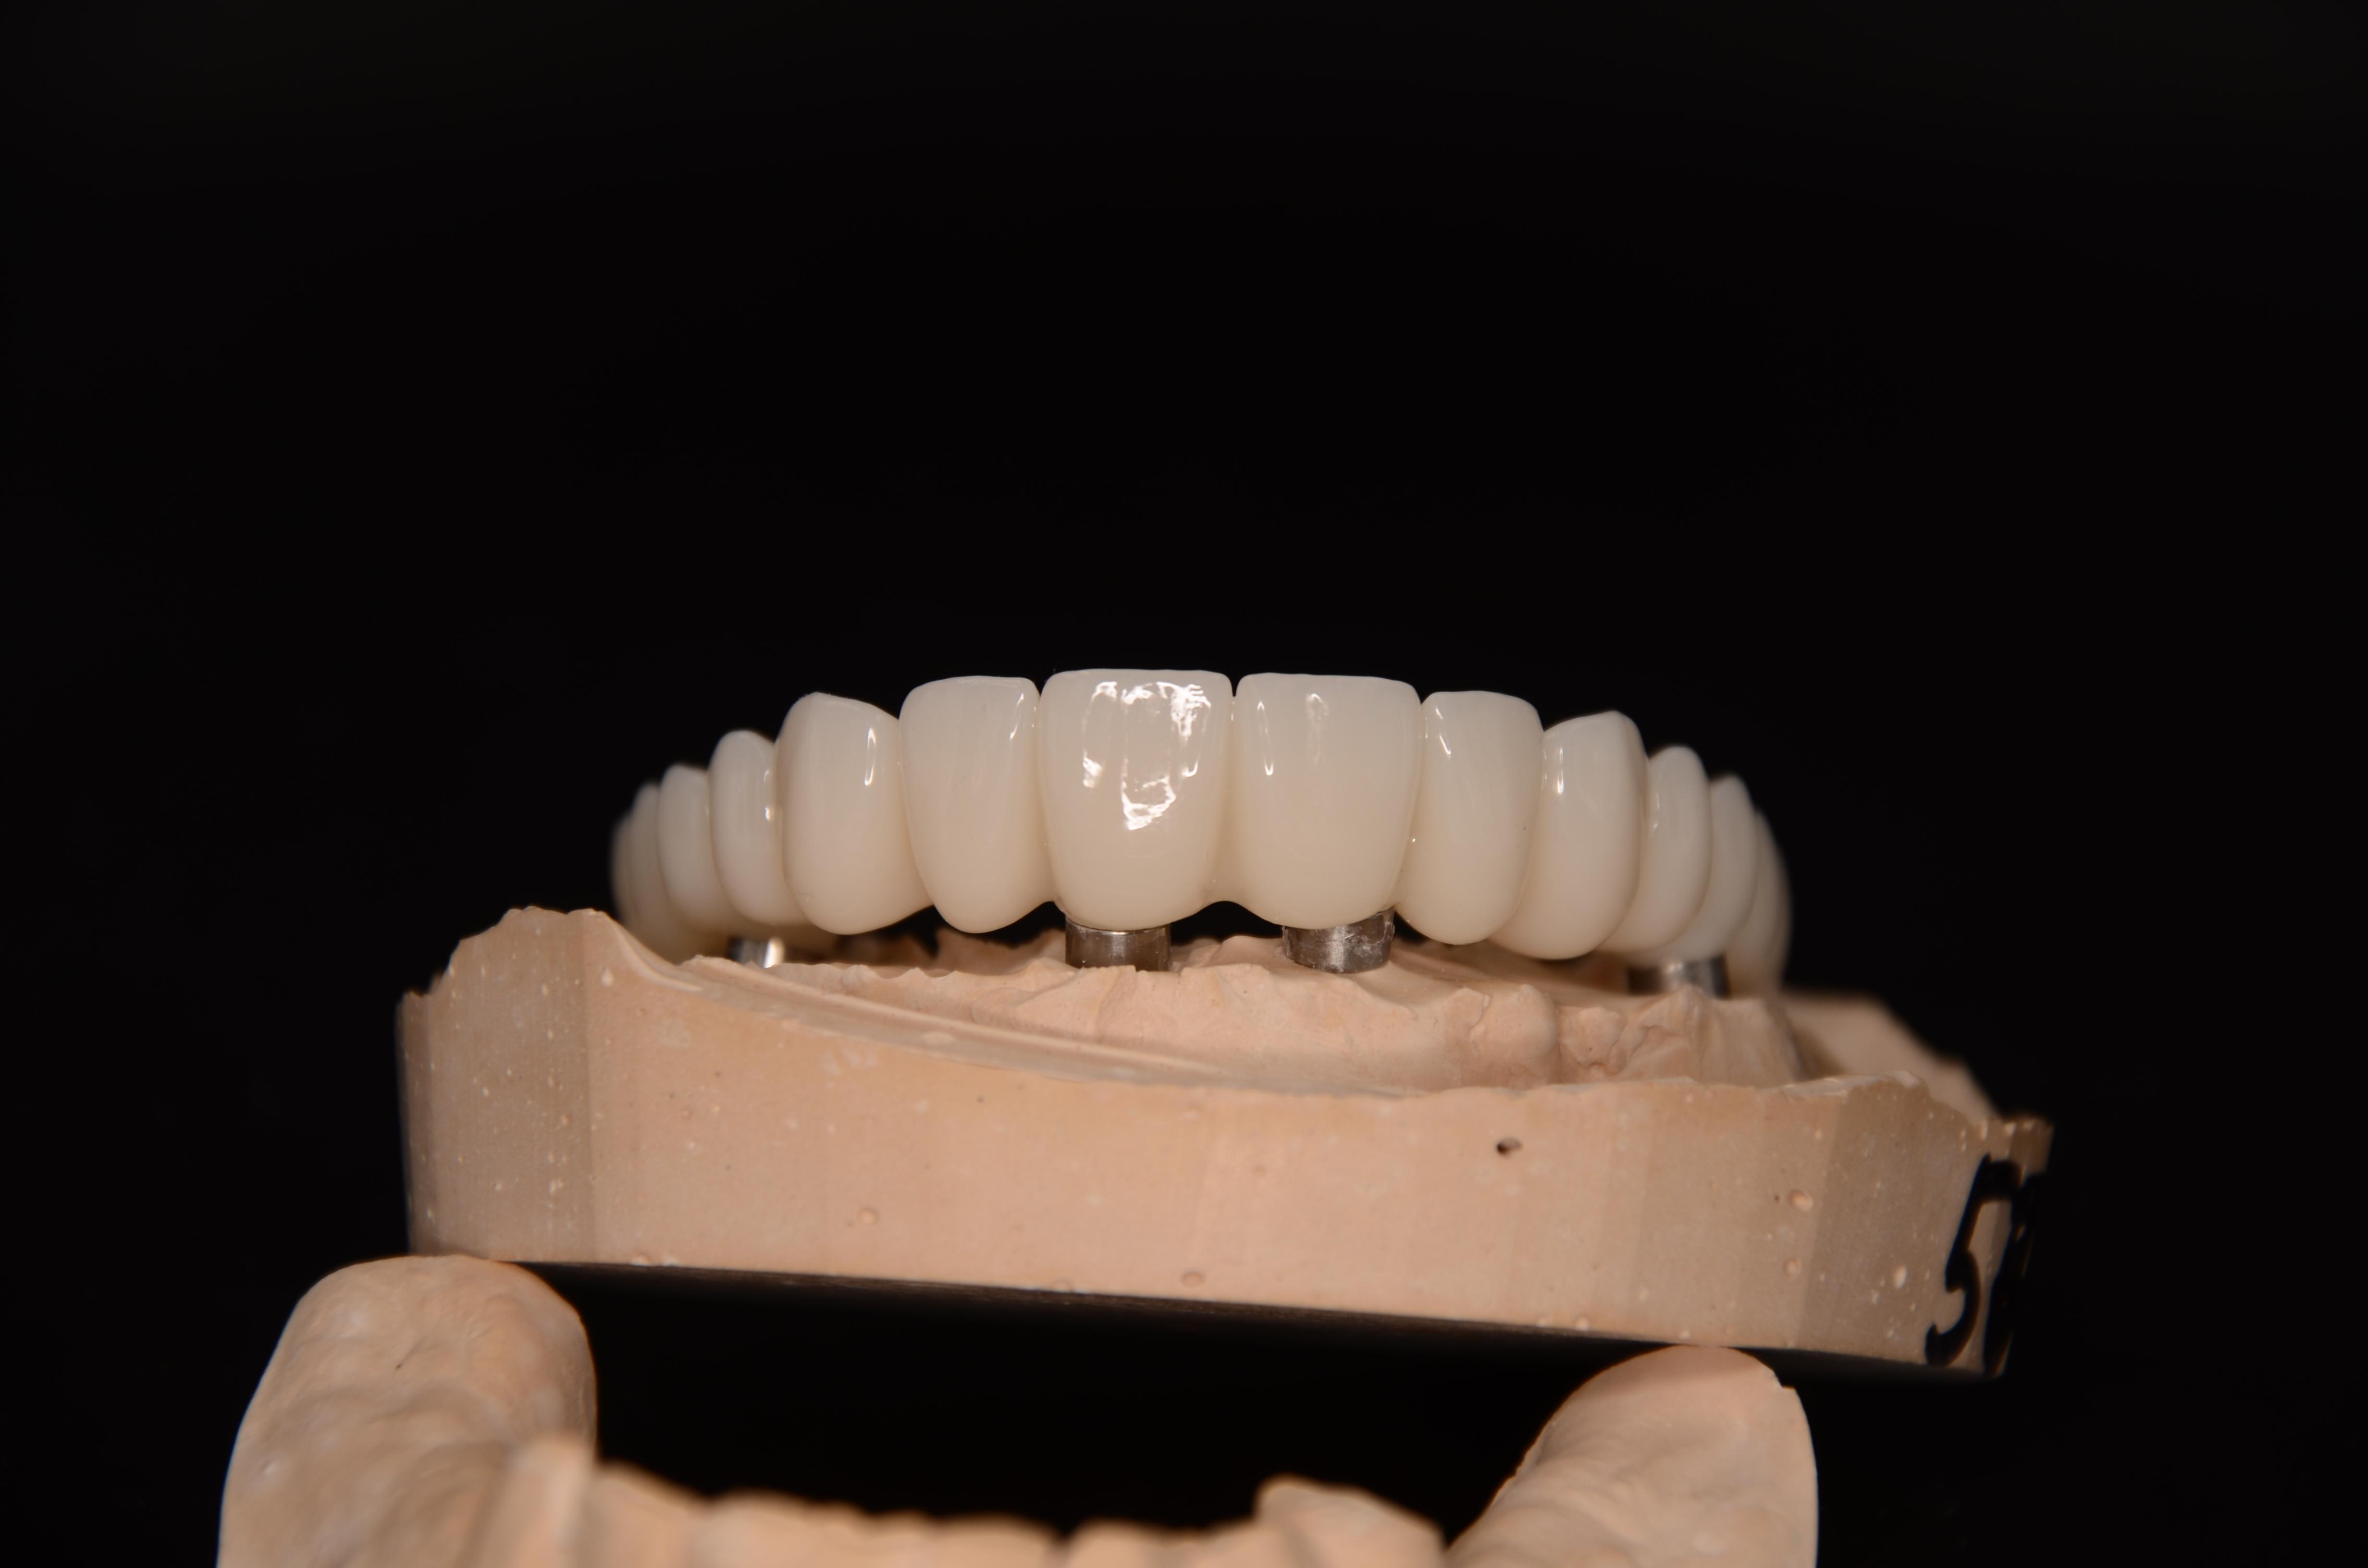

• Конструкция из Диоксида циркона All on X

200 000₽

• Конструкция из Титана/ Пластмассы All on X

150 000₽